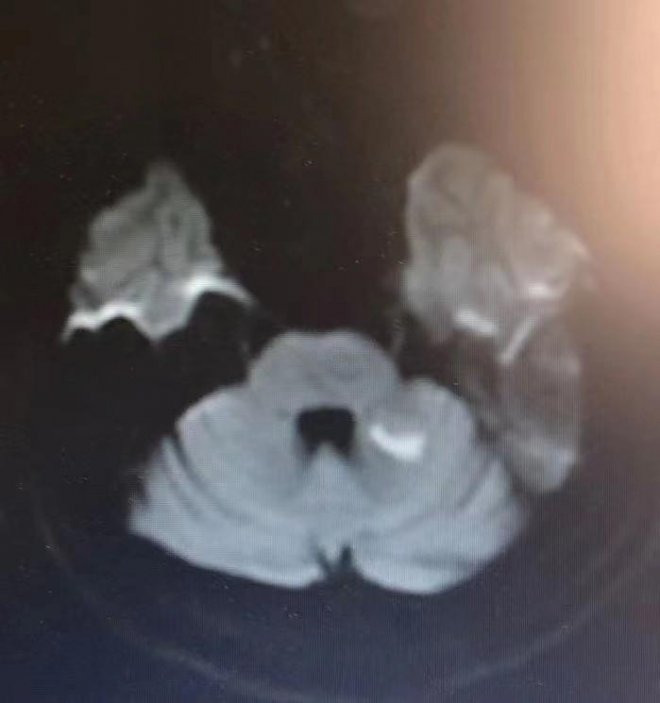

顱腦CT平掃結果出來後,確診了徐先生屬於急性腦梗死,雙側椎動脈重度狹窄。由於錯過了靜脈溶栓治療的黃金時間,醫生得採取別的方法進行治療。